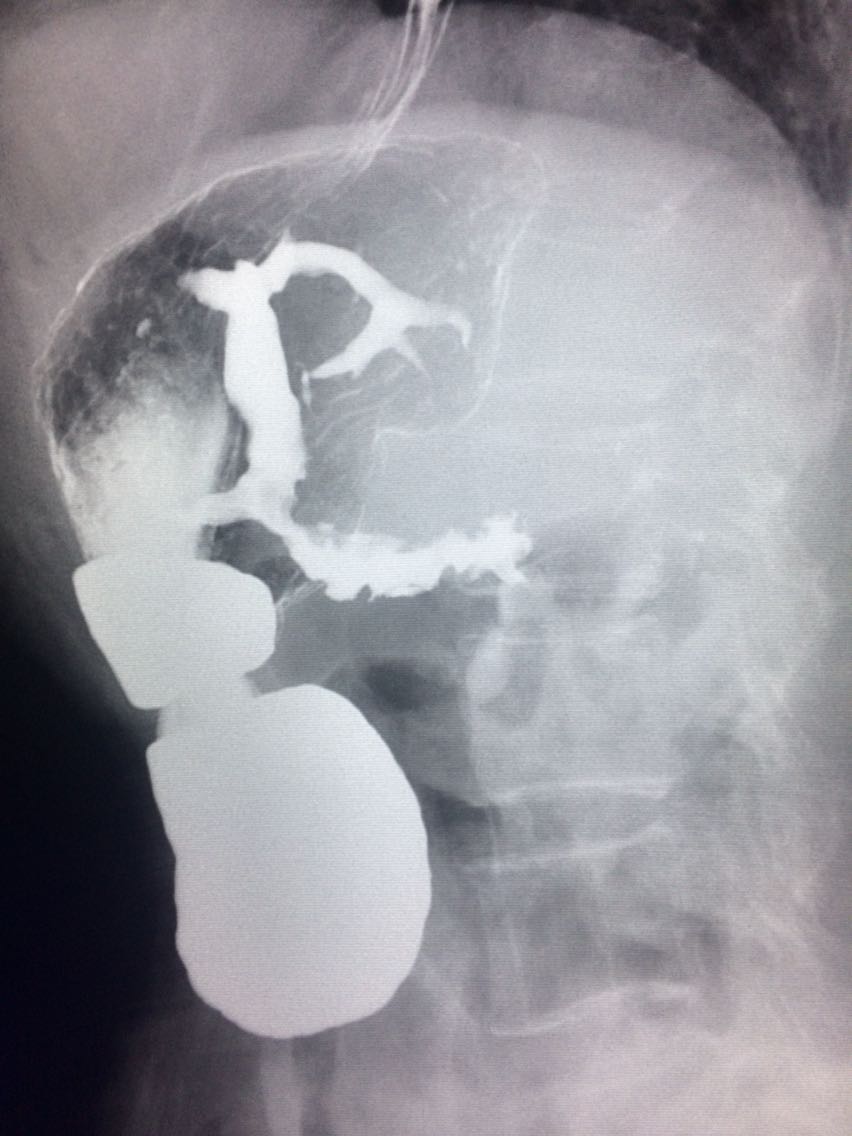

查体未见明显异常。 上消化道造影如图。

诊断食管癌。 造影剂逆流入胆道。